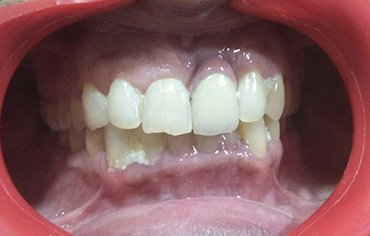

Missing teeth can significantly impact your confidence and overall appearance, making it difficult to achieve a perfect smile. Gaps in your teeth not only affect aesthetics but also lead to issues like difficulty in chewing, speech problems, and even jawbone deterioration over time. Fortunately, modern dental solutions like implants provide a permanent and natural-looking replacement. If you're looking for an Implant Center in Manjeri, you can get expert care and advanced treatment options to restore your smile seamlessly.